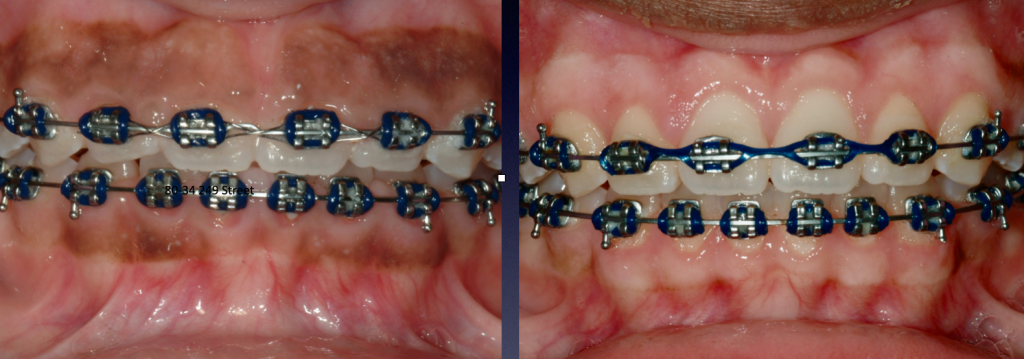

Gummy Smile Correction, with Braces